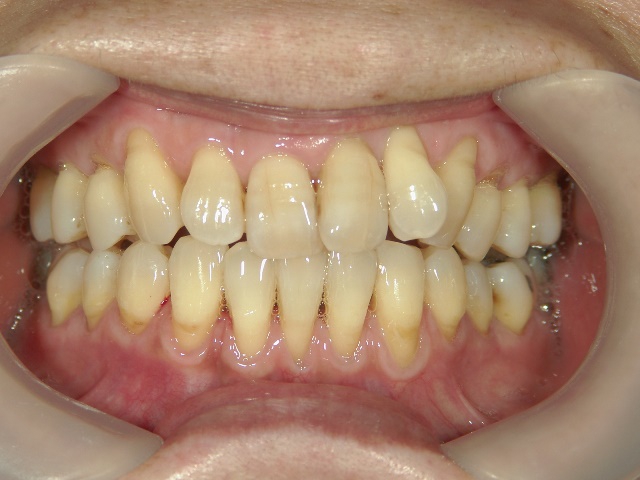

矯正歯科 治療前矯正歯科 治療前

矯正歯科 治療前

no.12_5333_治療前_左.jpgno.12_5333_治療前_正面.jpgno.12_5333_治療前_右.jpg

矯正_灰色.pngno.12_5333_治療前_下.jpg矯正_灰色.png